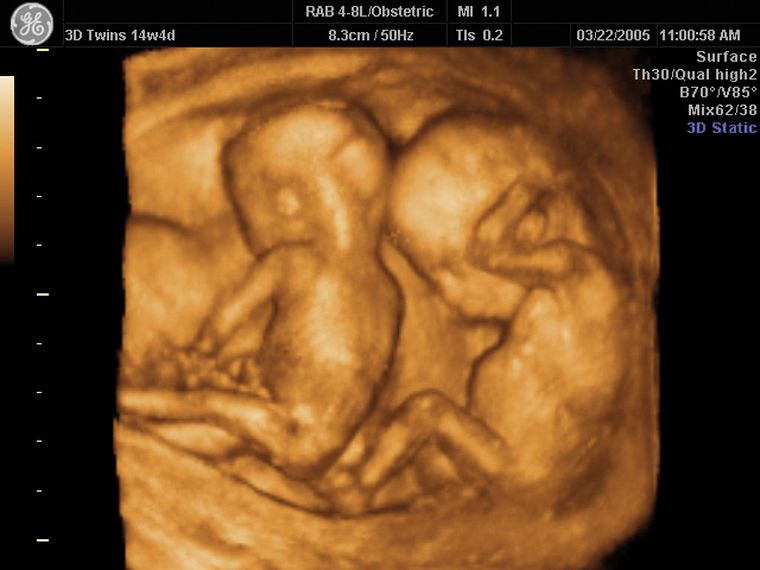

Antonia Herminia Juárez estaba embarazada de gemelos. Lo sabía porque ya le habían realizado cuatro ecografías. El martes a la noche se internó en el Hospital del Este, en Tucumán. La cesárea estaba programada para el miércoles a primera hora. Sin embargo, el final no fue el que esperaba: tras el parto, le entregaron un sólo bebé.